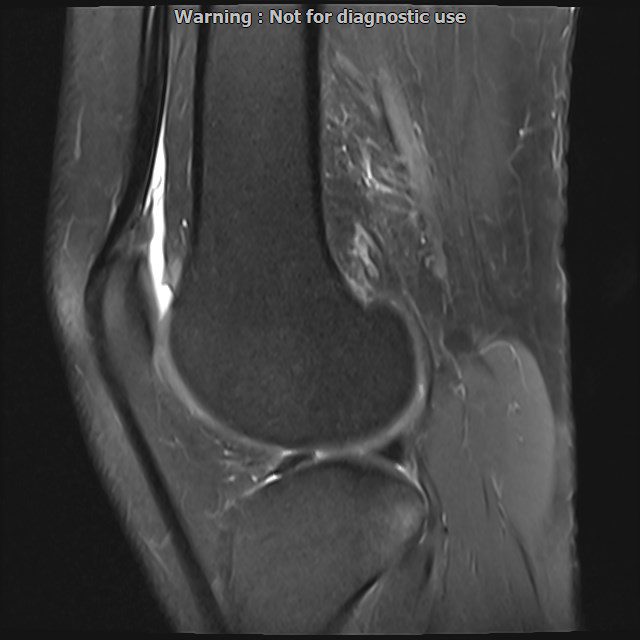

LEFT KNEE MRI

(Without contrast)

Siemens MRI ( magnetom altea 1.5 tesla )

Technique: Sagittal T1, Axial T2 fat sat, coronal & sagittal PD fat sat

The bones comprising the knee joint are normal in configuration

The cortical bone has normal thicknes

The hyaline cartilage covering patella, fermoral condyles and tibial plateau shows normal signal and thicknees

Medial and lateral meniscus displays normal configuration

PCL ,MCL & LCL are intacted

Patellar ligamentum and quadriceps tendon are normal in shape and signal intensity

– Mild knee joint effusion with soft tissue swelling around the knee

– Low grade partial tearing of ACL with kissing bone bruise in lateral of knee

are seen